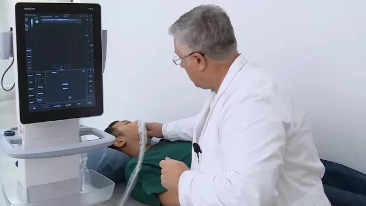

Desde que a empresa foi fundada, a Mindray est├Ī continuamente explorando novas maneiras de melhorar a confian?a no diagn├│stico. Alimentada pela mais revolucion├Īria tecnologia ZONE Sonography?, a nova plataforma Resona 7's ZST+ traz uma qualidade de imagem ultra-som a um n├Łvel superior por aquisi??o de zona e processamento de dados do canal.

Assim como o n├Łvel de qualidade de imagem premium, o Resona 7 tamb├®m melhora as capacidades de investiga??o cl├Łnica com o revolucion├Īrio Fluxo V para avalia??o hemodin?mica vascular e a aquisi??o de plano mais inteligente do conjunto de dados 3D para diagn├│stico CNS fetal. Combinando a opera??o mais intuitiva baseada em gesto de multi-toques e todos os recursos cl├Łnicos essenciais, Resona 7 est├Ī realmente conduzindo novas ondas na inova??o de ultra-som.